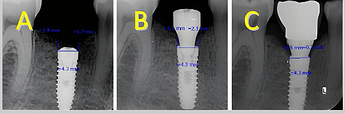

Crestal implant: (A) baseline (B) three months after placement (C) three months after loading

Subcrestal implant: (A) baseline (B) three months after placement (C) three months after loading

This study concluded:

The relationship between implant’s vertical position, soft tissue thickness and marginal bone loss is complex. While this research suggests that subcrestal placement and thinner tissues potentially lead to greater bone loss, more research is needed to fully understand the individual and combined effects of these factors. The time factor also significantly affects the amount of marginal bone loss, so the loss in the third month after implant placement is more than the loss in the third month after implant placement (six months after implant placement).